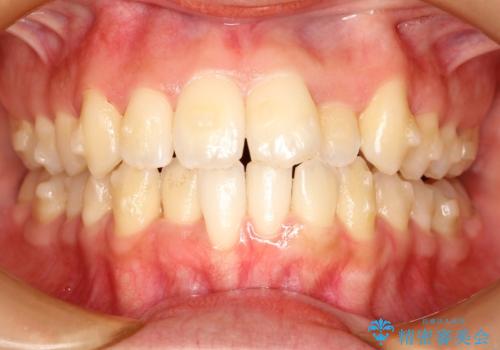

- 前歯の歯並びの改善を希望され来院された患者様です。

初診時の歯並びの状態としては、上下ともに全体に及ぶの中等度以上のがたつき(叢生)があり、前歯数本が反対交合の状態でした。

強い叢生がありましたが、抜歯は行わず上下顎ともに、主に歯列弓の拡大とディスキング(歯と歯の間に隙間を作る処置)を行い叢生を改善しました。